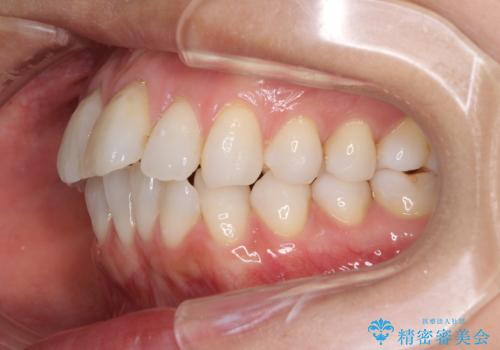

少しだけ飛び出た前歯を整えたい インビザラインによる矯正治療

- 少しだけ前に飛び出ている前歯を気にして来院された患者様です。

上顎歯列全体を後方に移動させる必要があり、インビザライン単体での治療は困難と判断し、補助装置により左右側方歯列を移動させた後にインビザラインを用いることとしました。